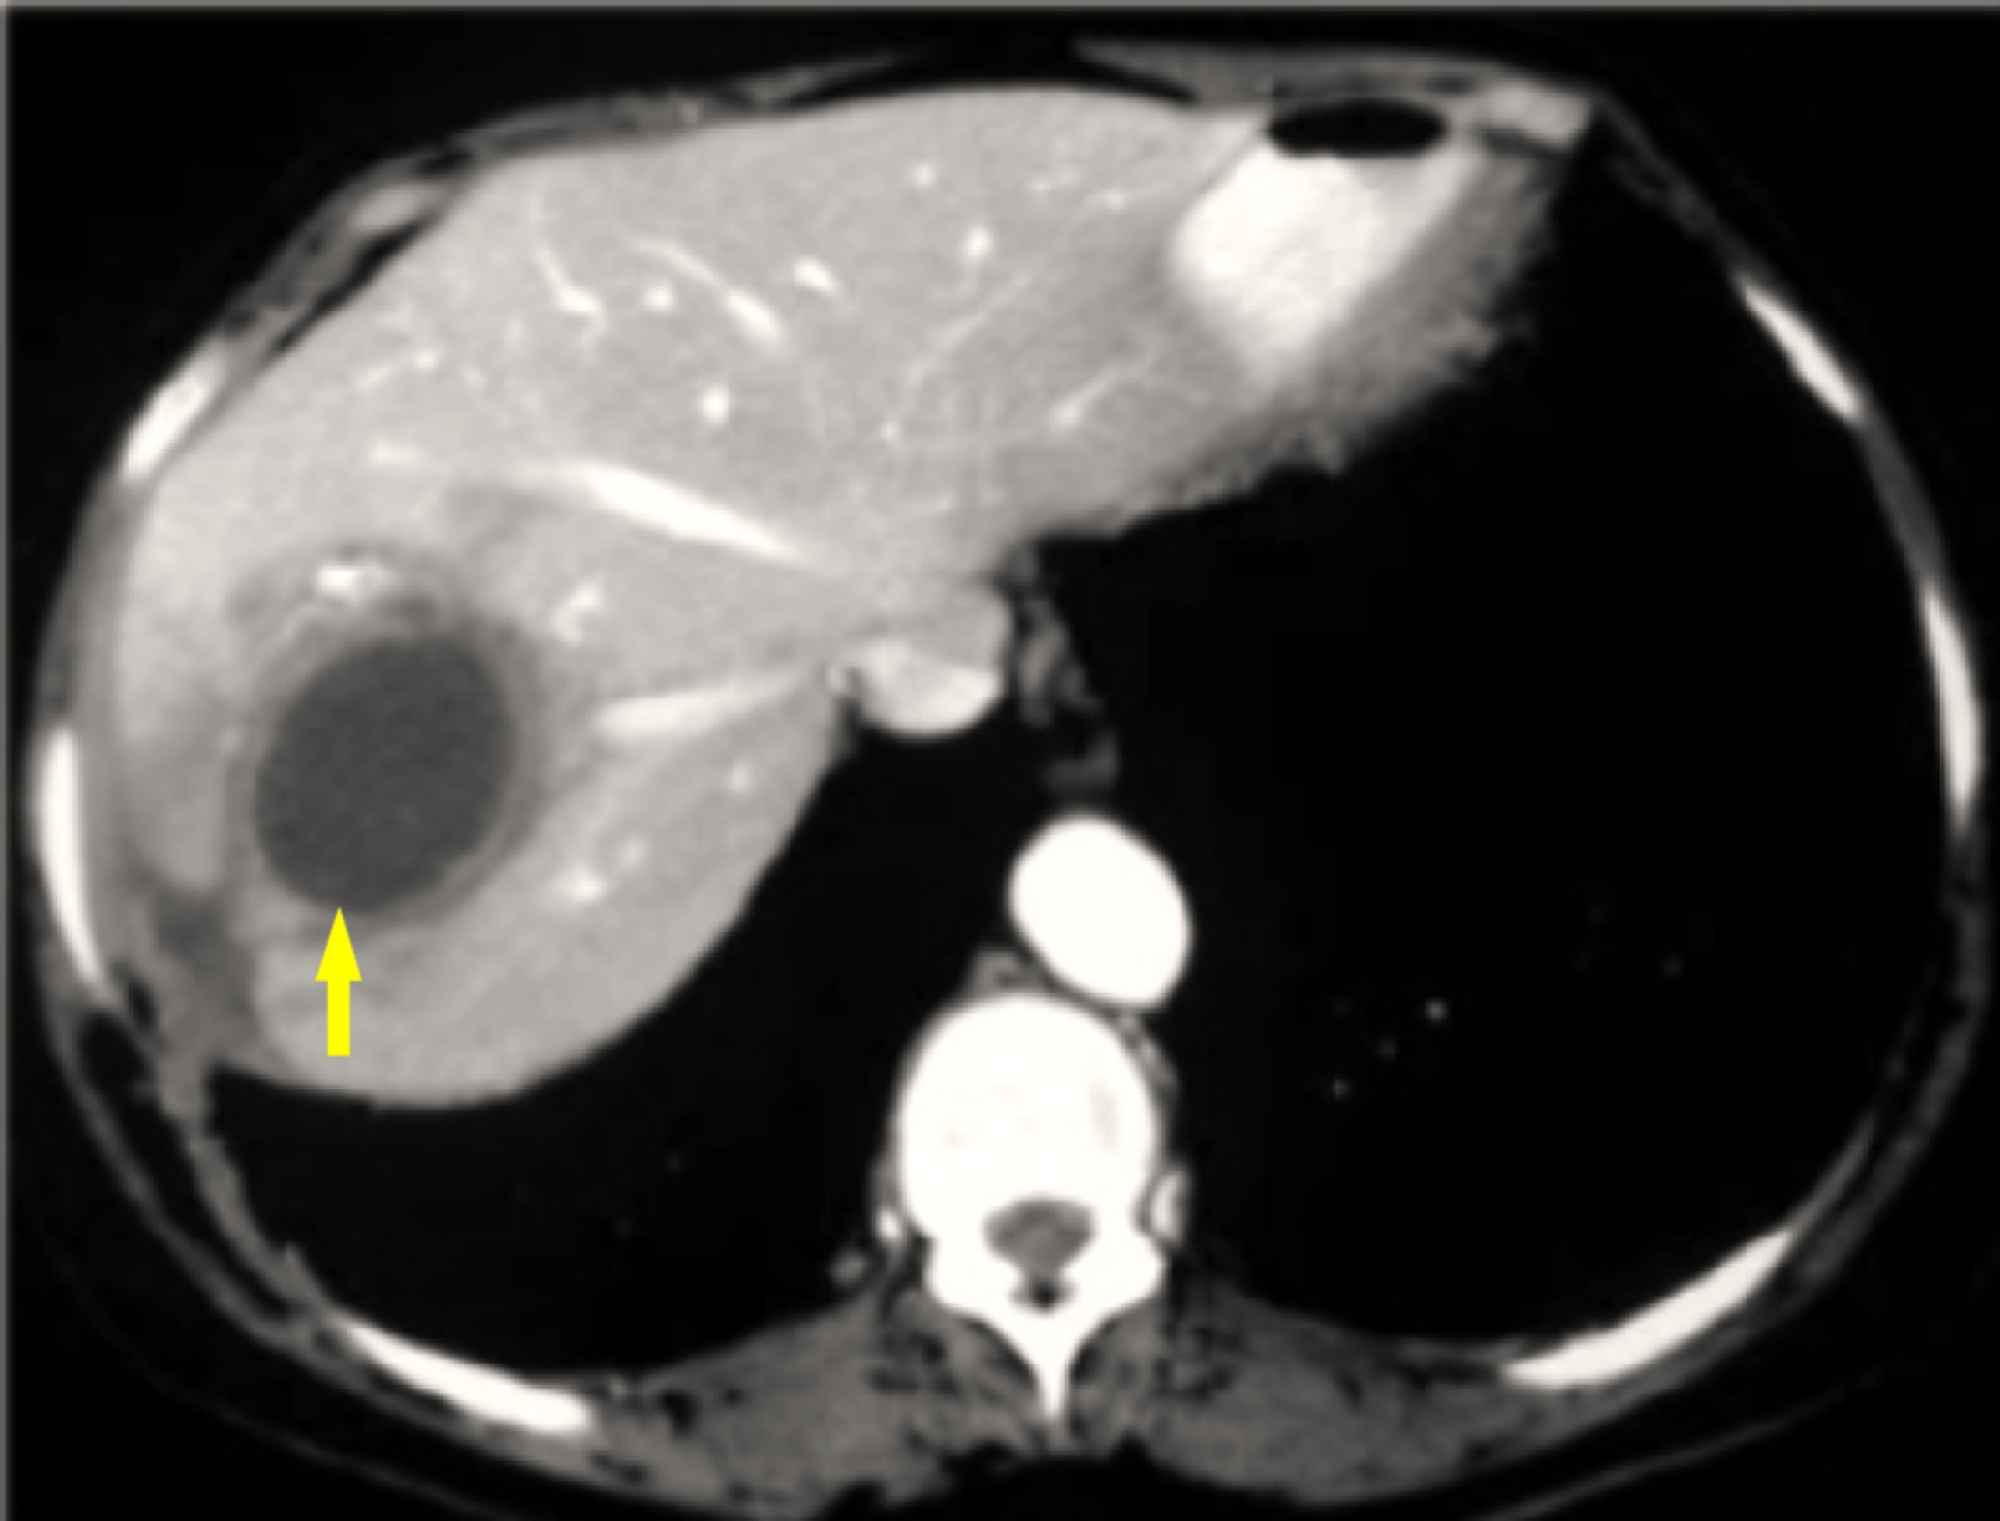

From www.thelancet.com

Pyogenic liver abscess caused by Streptococcus mitis The Lancet Strep Bacteria Liver A comprehensive overview of pyogenic liver abscess, a common type of visceral abscess, with causes, risk factors,. The impact of microbial pathogens on the liver can vary greatly, presenting with a wide variety of manifestations from asymptomatic elevations. Learn about gbs, a bacteria that can cause mild or serious infections in adults, especially those with medical conditions. Learn about the. Strep Bacteria Liver.

From www.cureus.com

Cureus Pyogenic Liver Abscess and Sepsis Caused by Streptococcus Strep Bacteria Liver The impact of microbial pathogens on the liver can vary greatly, presenting with a wide variety of manifestations from asymptomatic elevations. Streptococcal toxic shock syndrome (stss) is a rare, but serious bacterial infection. Learn about the different types of group a streptococcal (gas) infections, which can affect your skin and throat. Bloodstream infections are a serious complication in patients with. Strep Bacteria Liver.

Cureus Liver Abscesses Caused by Streptococcus intermedius in an Strep Bacteria Liver The streptococcus anginosus group includes three species: Streptococcal toxic shock syndrome (stss) is a rare, but serious bacterial infection. Learn about the different types of group a streptococcal (gas) infections, which can affect your skin and throat. A comprehensive overview of pyogenic liver abscess, a common type of visceral abscess, with causes, risk factors,. The impact of microbial pathogens on. Strep Bacteria Liver.

Cureus Liver Abscesses Caused by Streptococcus intermedius in an Strep Bacteria Liver The streptococcus anginosus group includes three species: Streptococcal toxic shock syndrome (stss) is a rare, but serious bacterial infection. A comprehensive overview of pyogenic liver abscess, a common type of visceral abscess, with causes, risk factors,. Learn about gbs, a bacteria that can cause mild or serious infections in adults, especially those with medical conditions. Bloodstream infections are a serious. Strep Bacteria Liver.